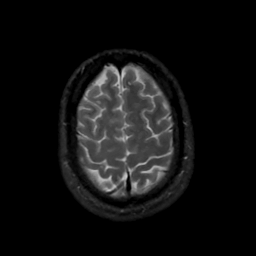

MR Study #16, June 23, 1991 -- Slice #42